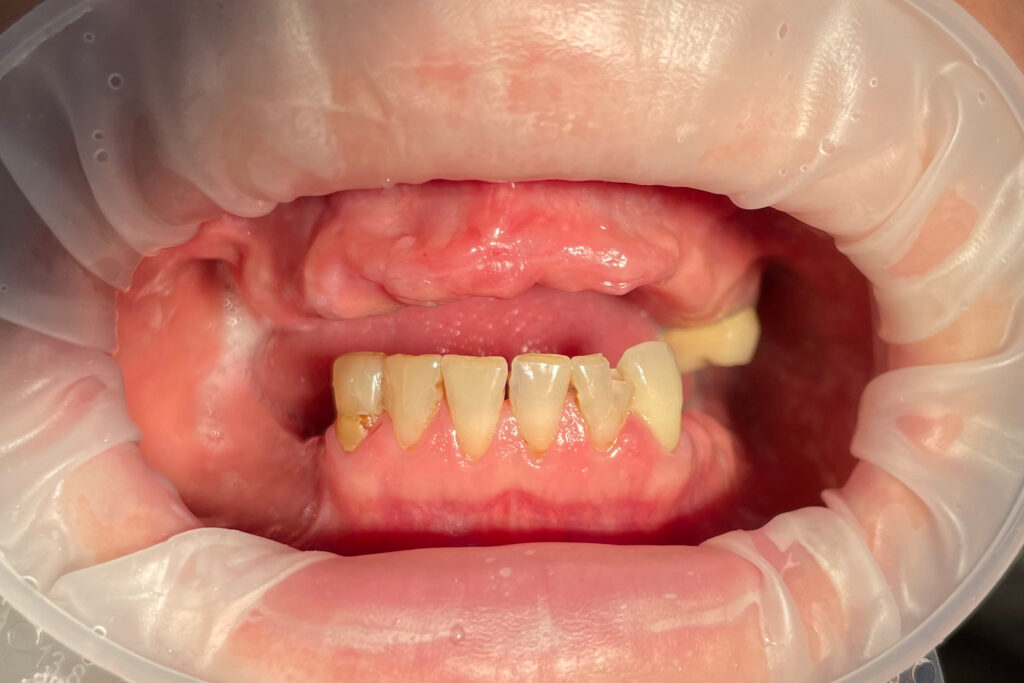

Ситуация до лечения

Жалобы: Пациент обратился к нам с целью имплантации верхней челюсти.

Диагноз: Полная адентия верхней челюсти и частичная вторичная адентия нижней челюсти.

пациент до имплантации